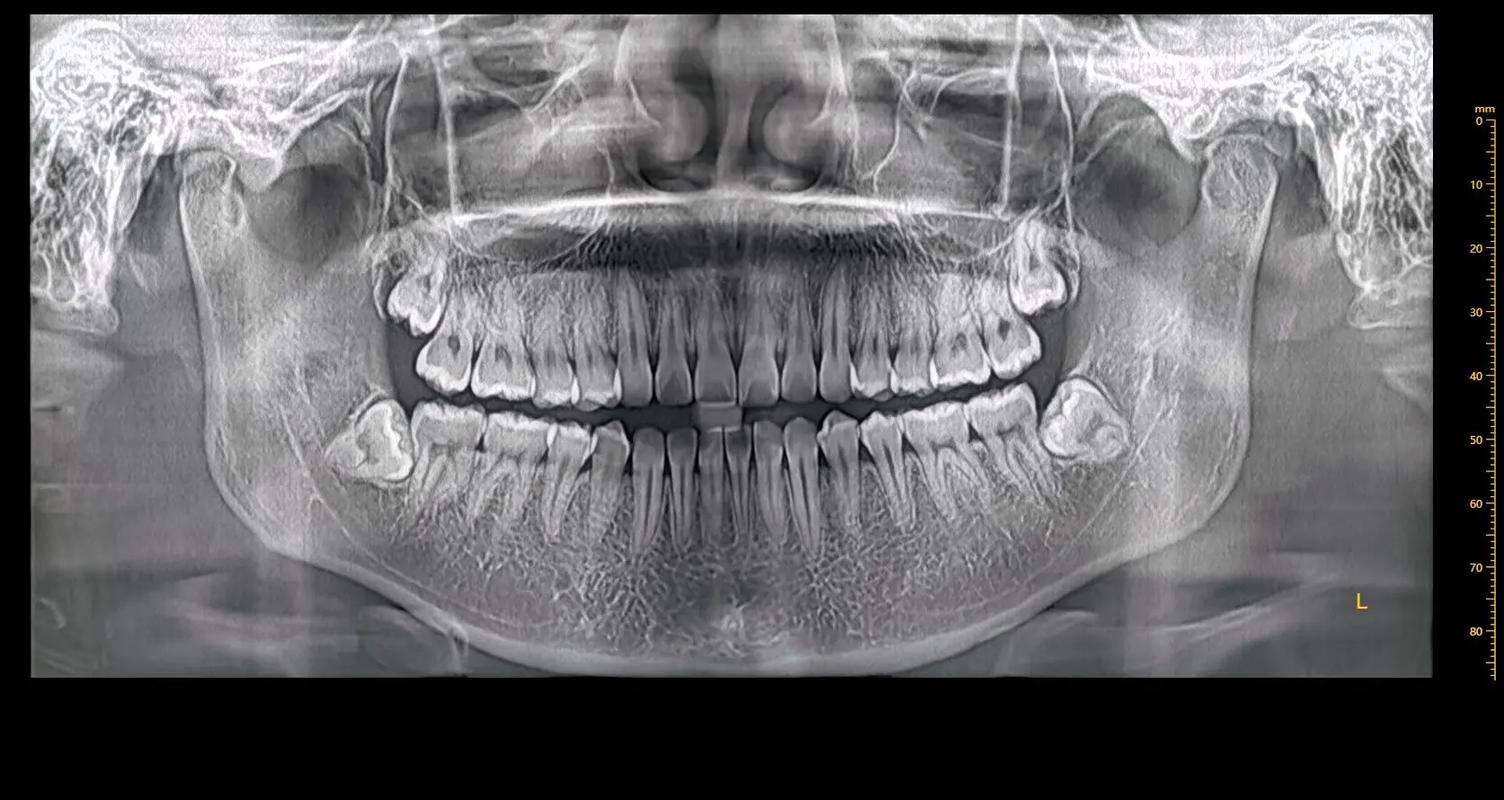

患者在口腔科就诊时,医生会根据不同病情,建议拍摄不同牙片,口腔科常用的牙片主要有这几种:口腔全景片。它可以把所有牙齿同时照在一张片子上,常用于观察全口牙齿、牙周、牙槽骨及上下颌骨肿瘤、外伤、炎症、畸形等病变及其与周围组织的关系等。但片子是二维的,无法观察三维结构。

口腔全景片是通过X光照射颌面部下1/3,可以显示全口牙齿、上下颌骨、颞下颌关节以及周围骨性组织的情况,在口腔临床很多治疗中都需要拍摄。

牙齿经常拍的两种片子包括牙片和曲面断层片,其中曲面断层片相对较为简单,一般需要患者站立好,相对应的牙齿微微张开,在规定的位置曲面断层片就可以扫到全部牙齿的情况。